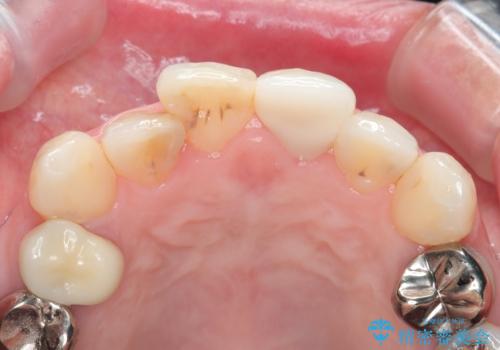

- 自転車で転倒してしまい、前歯を折ってしまい、痛みと見た目の改善を希望され来院されました。

もともと根管治療の為されて歯が折れてしまっているので、根管治療を行い審美的なセラミック治療を行う治療計画としました。

- 15.4万円(ジルコニアクラウン・仮歯・ファイバーコア)費用は治療当時の料金となります

周囲の歯と調和した審美的な仕上がりに満足いただくことができました。